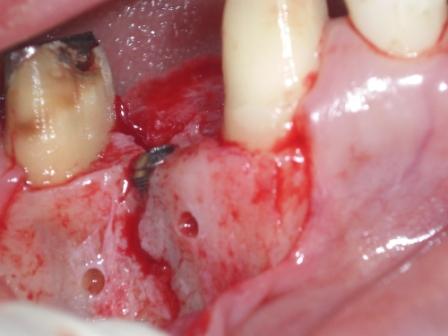

左上4番欠損、骨幅約2ミリ(歯槽頂)かなり細かったです。

かなり細いです ボーンスプレッターにて拡大

骨壊すことなく形成完了 頬側歯吸収性メンブレンにてGBRを行い終了。

アストラテック 4.0×11.0ミリ埋入